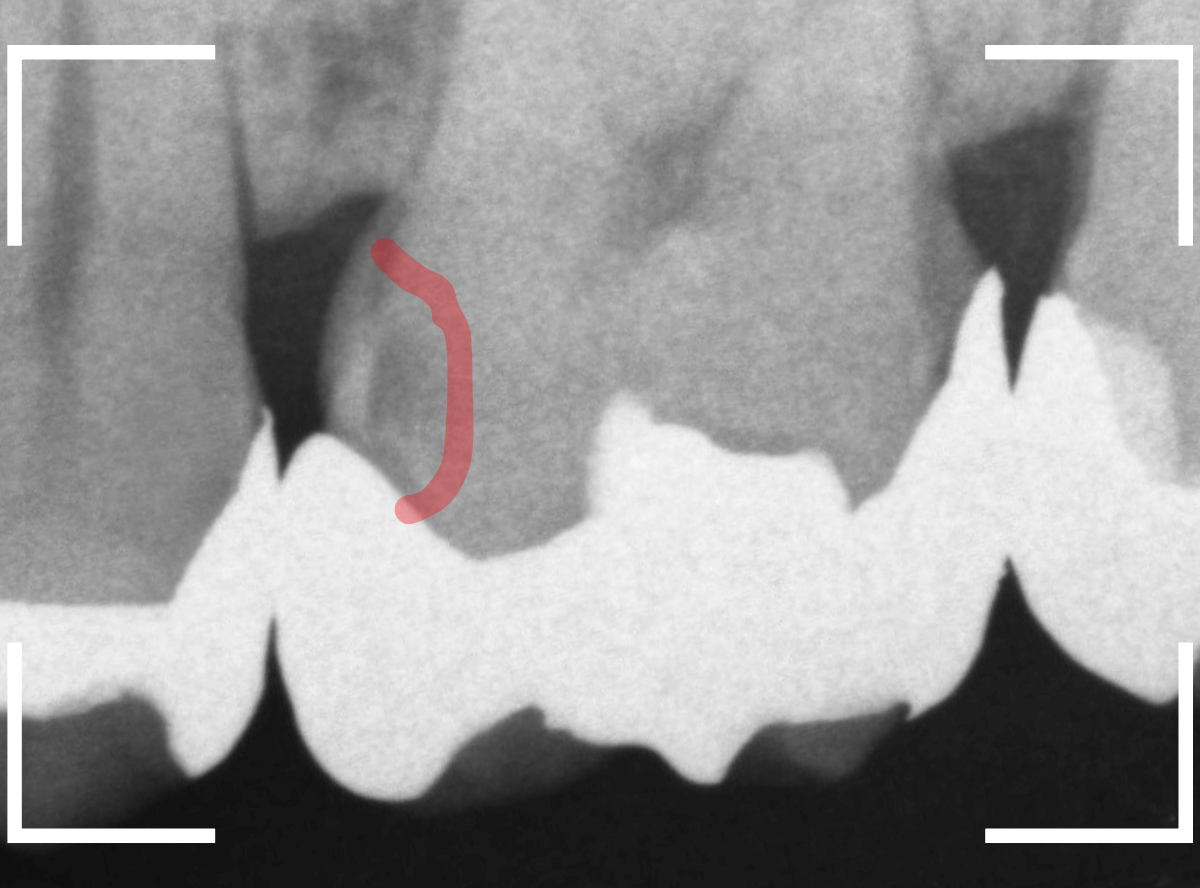

Case.14 インレーの下の歯肉まで広がった虫歯

レントゲン写真で確認します。

やはり、奥歯の端が大きな虫歯になっています。

青いラインが歯の神経、赤いラインが虫歯です。

レントゲン写真上では虫歯が神経まで達しているように見えます。

これは、神経を取らないとダメかもしれません。

赤い部分が虫歯と思われる部分、青い部分が歯の神経です。

確認すると、インレーの下まで虫歯が進行している可能性があります。